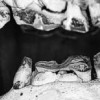

Are you getting value from your  Equine Dental Service Provider?

Value for money is one of the key parts of choosing any product or service, but equine dentistry is a complex service. How do you, the horse owner or trainer, decide on whether you are getting value or not from your service provider? In this article, we show you how you can cut through the cloud of uncertainty and calculate what you should be paying for quality equine dentistry, and what you should be getting for your money!

Is Sedation Necessary?

Today's "state of the art" equine dentistry requires sedation to safely and effectively perform the in-depth, complete examination of the teeth and oral cavity and the treatments necessary for maximum…

Some Indications of Equine Dental Problems

Some symptoms that can alert you to dental problems in your horse are: loss of feed from the mouth while eating slowness of eating head tossing with or without contact …